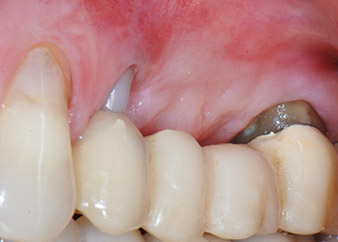

Two-months interim result

Figures 17 and 18 show the clinical result two months after the surgery. Tooth 24 exhibited reduced mobility of Miller class 1, and the soft tissues were free of inflammation. Probing was avoided at this point of time to prevent reinfection and to avoid violating the epithelial attachment. A control visit was scheduled for reentry and placement of healing abutments, six months after the insertion of the implants.

Two months after the surgery, the patient was pain-free.

Fig. 17: Two months after the surgery, the patient was pain-free and the area was free of inflammation.

after the surgery

Fig. 18: Tooth 24 now showed less mobility.